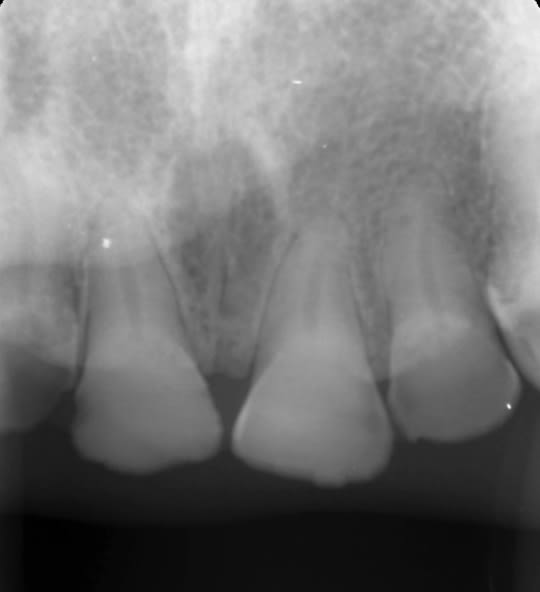

Radio 16